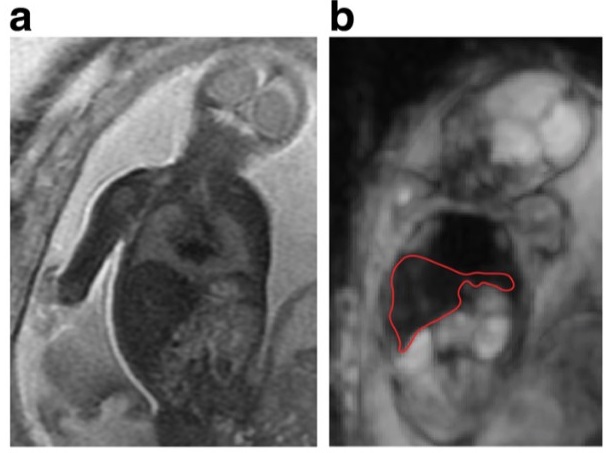

The aim of this study was to test the within-subject (test–retest) reproducibility of the perfusion fraction, diffusion coefficient, and pseudo-diffusion coefficient measurements in various foetus organs and in the placenta based on the intra-voxel incoherent motion (IVIM) principle. The results concluded that IVIM magnetic resonance imaging could potentially provide a novel method for examining microvascular perfusion and diffusion in the developing human foetus.

•    Foetal IVIM imaging portrays foetal organ and placental microvascular perfusion

•    Repeatability of IVIM-derived values are moderate for the placenta, foetal lungs and liver

•    Foetal IVIM imaging requires advanced image post-processing and analysis